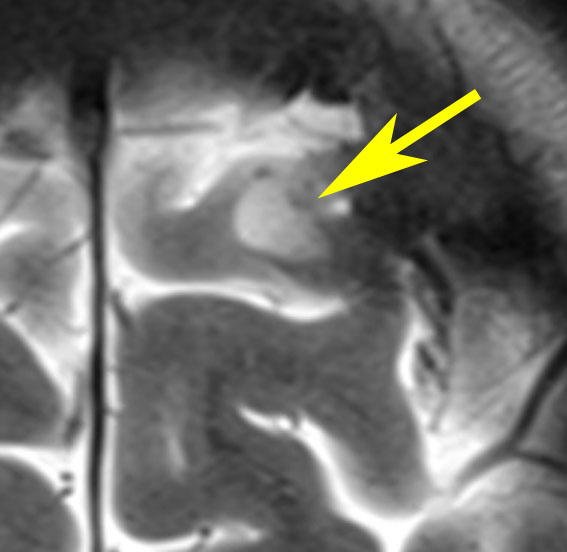

脳と腰部のガドリニウム増強MRIです。腫瘍は白く見えるようにしてあります。黄色の矢印で示した以外にも無数の神経鞘腫があります。